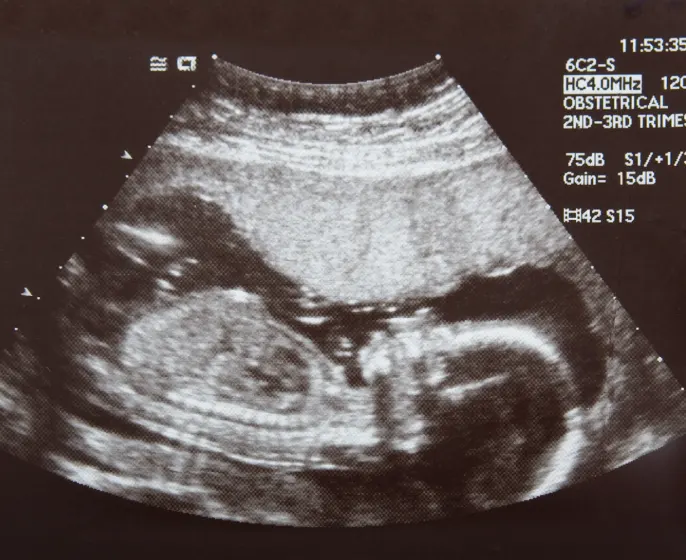

Ultrasound technology uses high-frequency sound waves to create images of organs, tissues, and blood vessels in real time. This is a non-invasive procedure and does not include the use of radiation. Ultrasound is commonly recommended for visualizing the development of the fetus and is used in other medical specialties to evaluate various health conditions.

• Ultrasound helps in the better monitoring of a fetus in the womb.

• It also detects problems in the bladder, uterus, fallopian tubes, etc.

On the other hand, ultrasound is an integral part of medical diagnostic, it can be used to visualize internal organ, evaluate joint tendon, guided injection and much more.